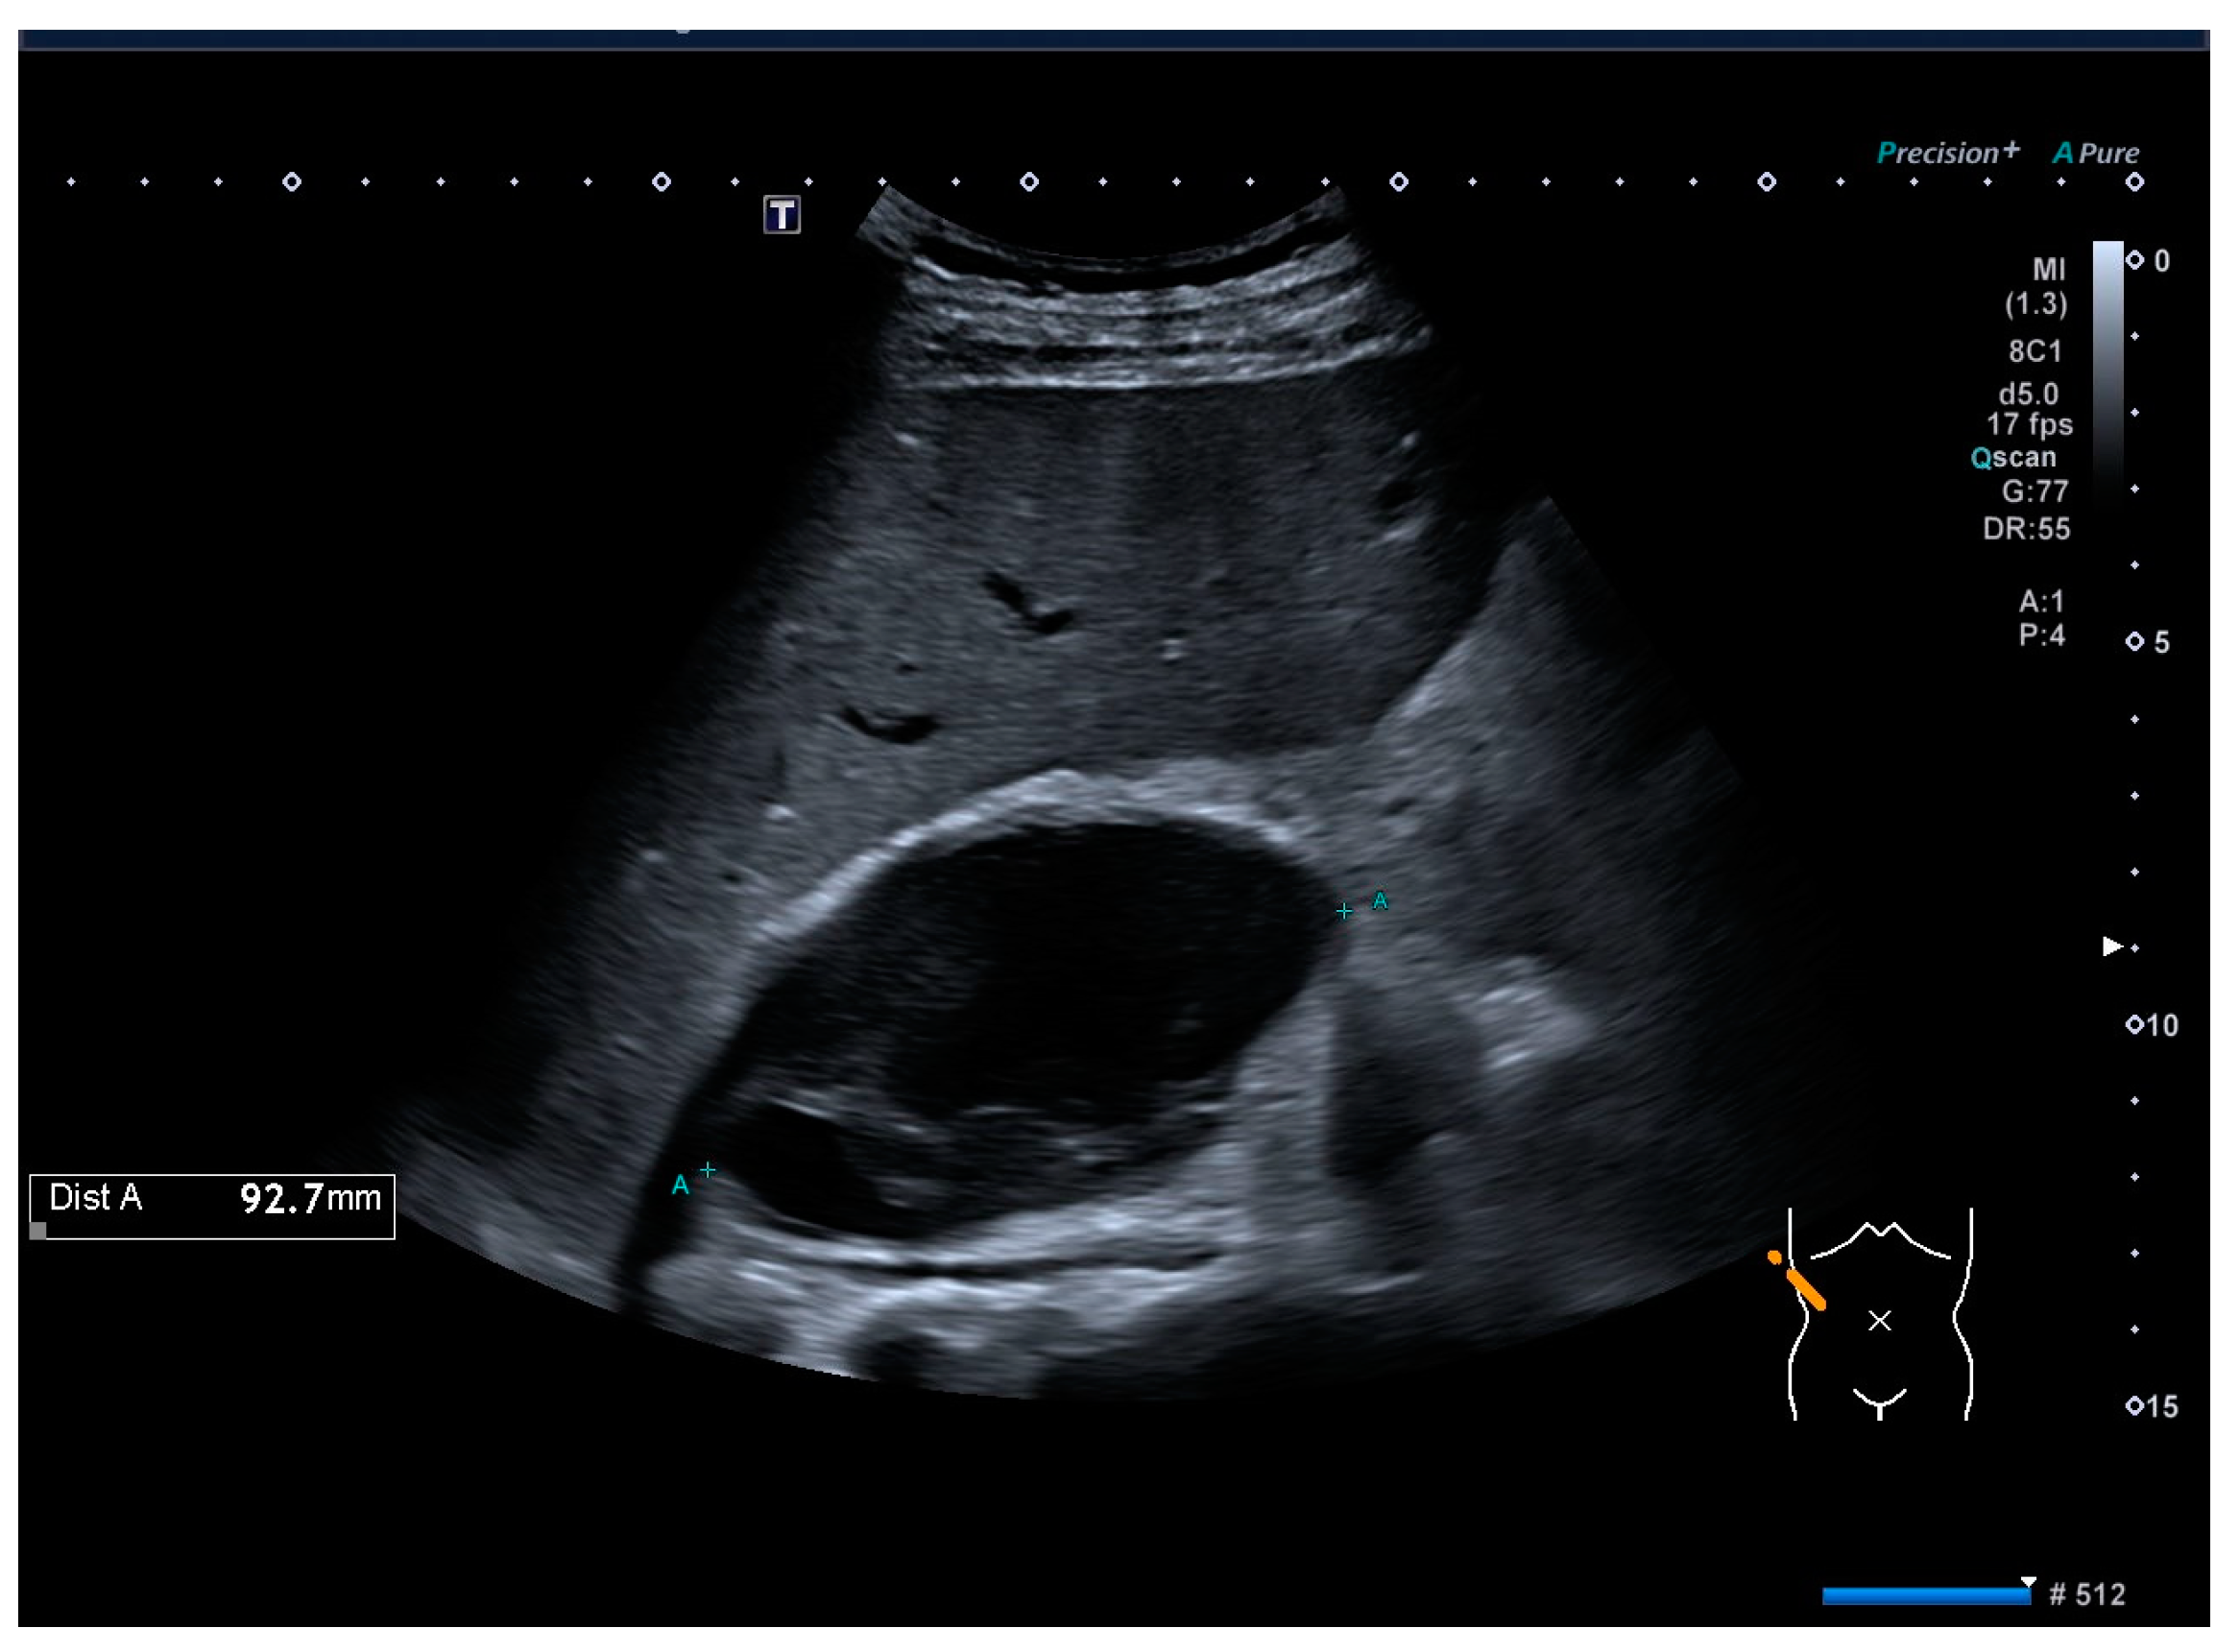

A control CT was performed three months after the cesarean section. The CT scan demonstrated a reduction in the size of the hematoma, which was measured at 28 × 23 × 11 mm (Figure 3). The patient continues to be managed by an endocrine surgeon.

Figure 3. Abdominal CT scan. A hematoma is present in the projection of the right adrenal and is markedly smaller in size than that observed in the MRI performed three months ago.